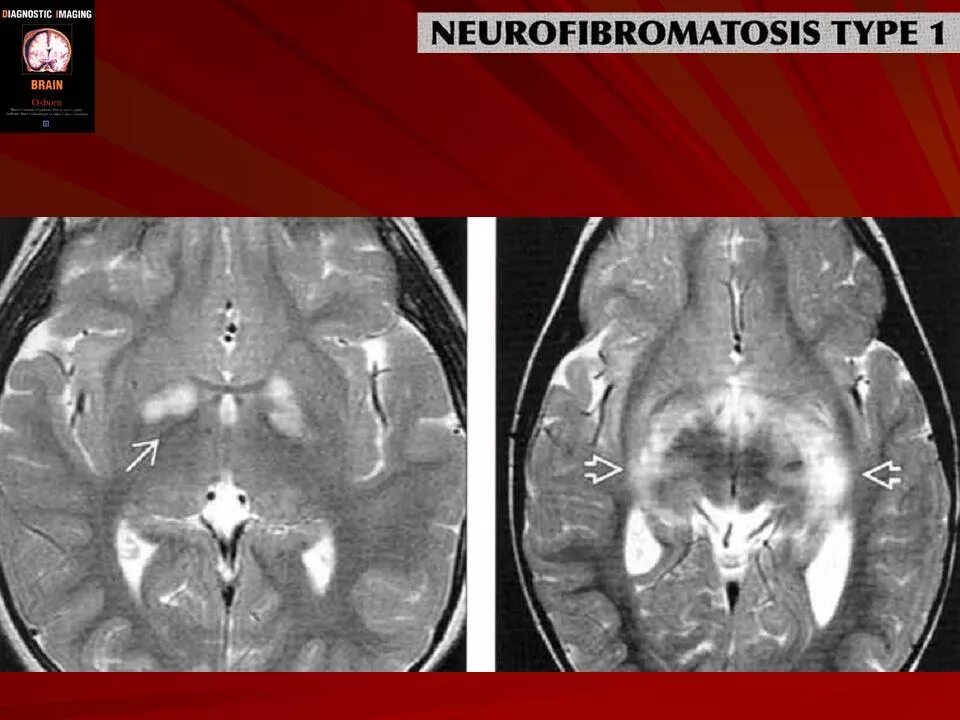

Нейрофиброматоз мрт